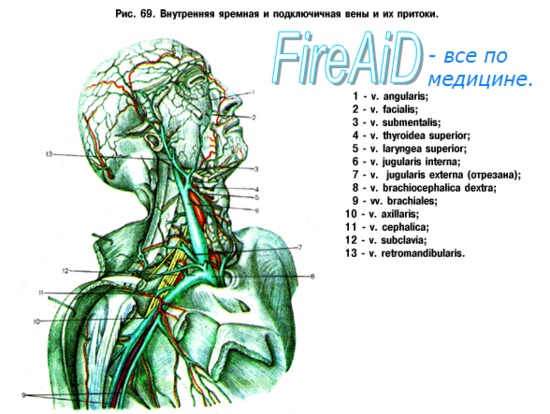

Анатомия внутренней яремной вены: КТ изображения